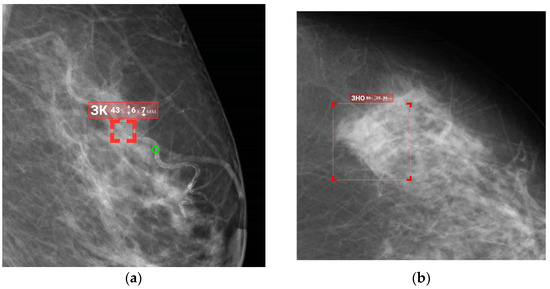

2.5.2. Functional Testing

| 1 | Detection, segmentation, and classification (benign/malignant) of masses | Graphical mask, text | DICOM, DICOM SR, Apache Kafka message |

| 2 | Detection, segmentation, and classification (benign/malignant) of calcifications | ||